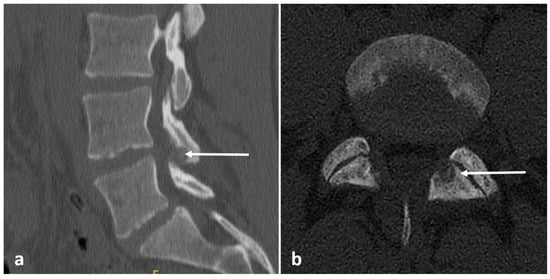

3.2. Osteoid Osteoma

| Osteoid osteoma | Lucent nidus, usually 2–10 mm. May be surrounded by sclerotic rim. | Surrounding marrow oedema on fluid sensitive sequences (best seen on STIR). Nidus can be occult on MRI. |